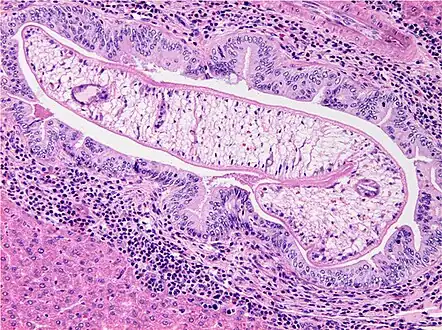

Photomicrograph of an adult O. viverrini in bile ducts of experimentally infected hamster -

Generally, opisthorchiasis due to O. viverrini is harmless without any clinical symptoms. Mild symptoms may appear such as dyspepsia, abdominal pain, constipation, or diarrhoea. However, under severe infection, enlargement of liver (hepatomegaly) and malnutrition are observed. In rare cases, cholangitis, cholecystitis, and cholangiocarcinoma can also develop. In humans,O. viverrini inhabits mainly the bile ducts, and rarely, the gall bladder and pancreatic duct. Heavy infection can produce problems in the liver, gall bladder, and bile ducts. The bile ducts of heavily infected patients are usually dilated and indicate fibrosis.[24][25] Pathological effects on the bile ducts include inflammation, epithelial desquamation, goblet-cell metaplasia, epithelial and adenomatous hyperplasia, and periductal fibrosis.[26] The collective effects in addition to specific parasite secretion and the host's immune reactions account for the development of cholangiocarcinoma. The infection is not immediately life-threatening; cancer develops after 30–40 years, but death occurs very fast, within 3–6 months of diagnosis.[17]